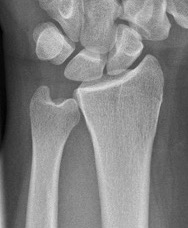

Xrays

Ulna variance

Wide variation in the population - increased load on TFCC with ulna positive

Xray in neutral supination / pronation

- variance is not static and varies up to 3 mm with wrist position

- ronation increases ulnar variance

- supination decreases variance

Transverse line of lunate fossa to transverse line of ulna head

Ulna neutral

Ulnar negative

Ulna positive